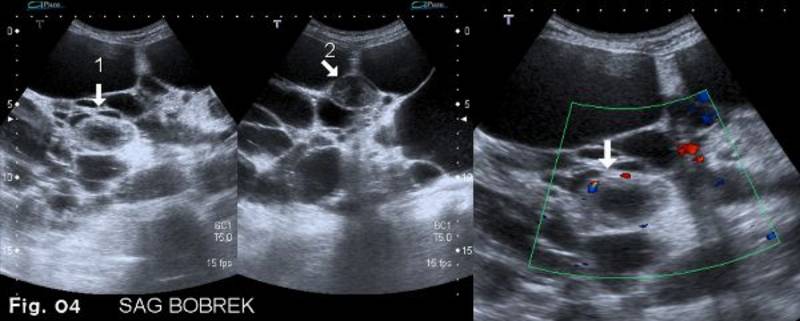

Pacientam hematūrija turpinājās arī pēc operācijas un tika atkārtots USG izmeklējums. Šajā reizē labajā nierē tika atklātas divas kompleksas cistiskas masas, kas sākotnēji nelikās aizdomīgas (4. attēls).

Tā kā hematūrija turpinājās un pacients jau tika gatavots nieru transplantācijai, tika izoperēta arī labā niere. Histoloģiskajā izmeklēšanā atklājās tikai kompleksas labdabīgas cistas bez malignitātes.